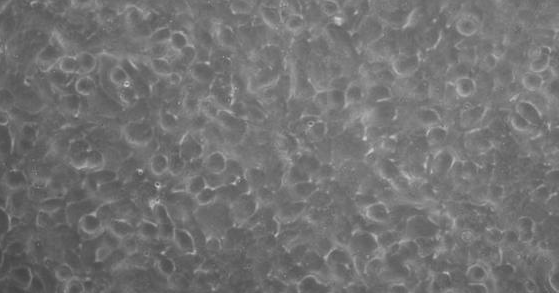

贴壁;上皮细胞样

形 态:贴壁;上皮细胞样

4. 将培养瓶平放使胰酶浸没整个瓶壁的细胞层,计时约40s,立马竖起对着灯光可观察到细胞与NCI-H1930细胞之间有针孔样缝隙,并有1-2个细胞脱落,这时为胰酶消化的最适时机。若看到成片的细胞从瓶壁脱落为胰酶消化过度;若看不到针孔样缝隙和细胞脱落,则需继续消化,轻轻的迅速平放培养瓶使胰酶浸没细胞层1s后迅速竖起对着灯光观察细胞情况,可反复几次,直至出现针孔样缝隙和1-2个细胞脱落的最佳消化状态。用移液器将胰酶吸净。

每天定时观察NCI-H1930细胞生长情况,一般72-96h后,细胞生长密度大于90%,即可进行细胞的传代或保株。

文献和实验都是贴壁细胞,在消化传代过程中,步骤如下:倒尽旧的培养液->用无血清的培养基清洗一两次->加入一定量的胰酶,置于37度培养箱中5--10分钟,使细胞悬浮->显微镜下观察,待细胞大部分变圆时,回到超静台->加入一定量的含血清的新培养液,以终止胰酶作用->反复吹打细胞->再置显微镜下观察,直到细胞全部悬浮起来->吸出一部分加入新的培养瓶中->最后再补充加入一定量新的培养液。注意: 1、吹细胞时尽量多吹边角儿,此处细胞生长的多。2、吸出细胞前要混匀,可以剧烈震荡培养瓶。3、我们用的是DMEM